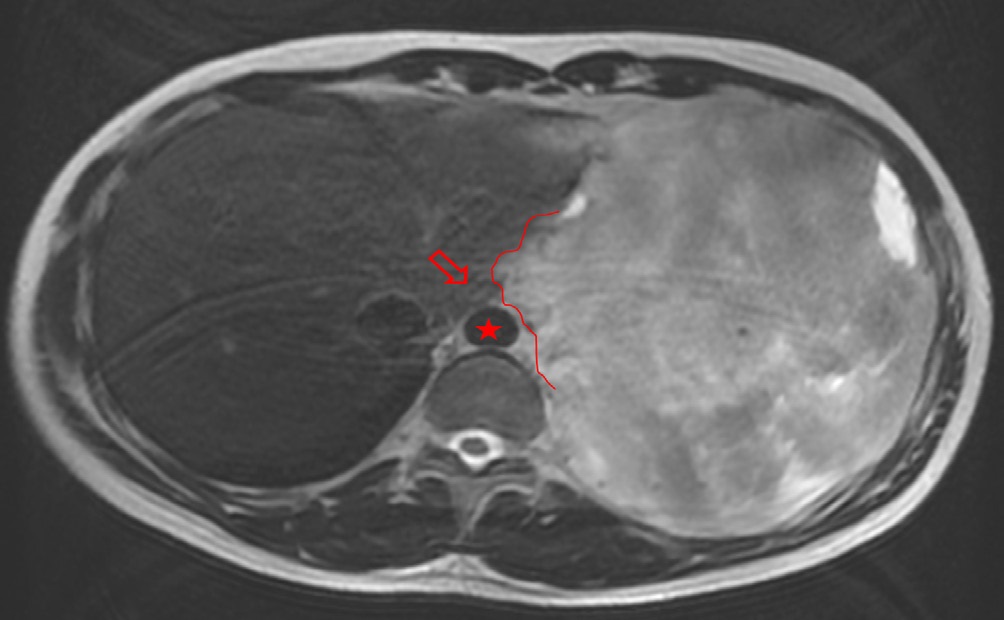

A 28-year-old male patient presented with onset of pain on his left hemithorax and progressive fatigue, in September, 2020. He had no previous comorbidities. An investigative MRI (magnetic resonance imaging) scan showed a large and heterogeneous mass on his left hemithorax with partial lung atelectasis, inferior displacement of diaphragm, mediastinal shift to the right and small pleural effusion (Figures 1a, 1b and 1c). The tumor was in contact with the inferior esophagus and the descending aorta. The thoracic wall (muscle and ribs) was not compromised. These findings suggested, possibly, a mass of pleural origin. An initial core-needle biopsy was performed in October, 2020 to clarify the diagnosis.

Figure 1a: Large solid mass (24 x 10.5 x 14.5 cm) with hemorrhagic areas and heterogeneous post contrast enhancement on the left pleural space.

Figure 1b: The lesion pushes downward the diaphragm, promotes lung atelectasis and displaces mediastinal structures to the right. Minimum pleural effusion is associated (x).

Figure 1c: The mass also and extends to the posterior mediastinal fat (line) close to the descending aorta (star) and esophagus (empty arrow).